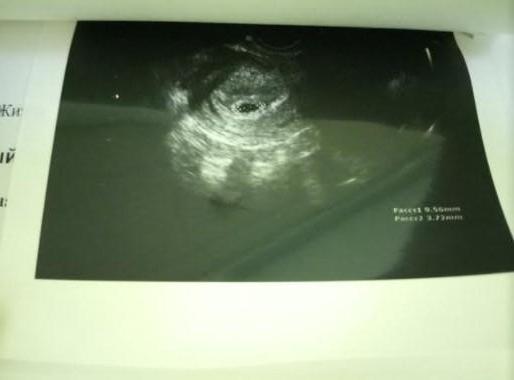

На узи плодное яйцо. Маленькая радость.

Ну по снимку нет у вас какого-то сдавленного плодного яйца или чего-то супер страшного. Гипертонус может быть тупо от узи. Пока ведите спокойный образ жизни и сделайте еще узи через неделю.